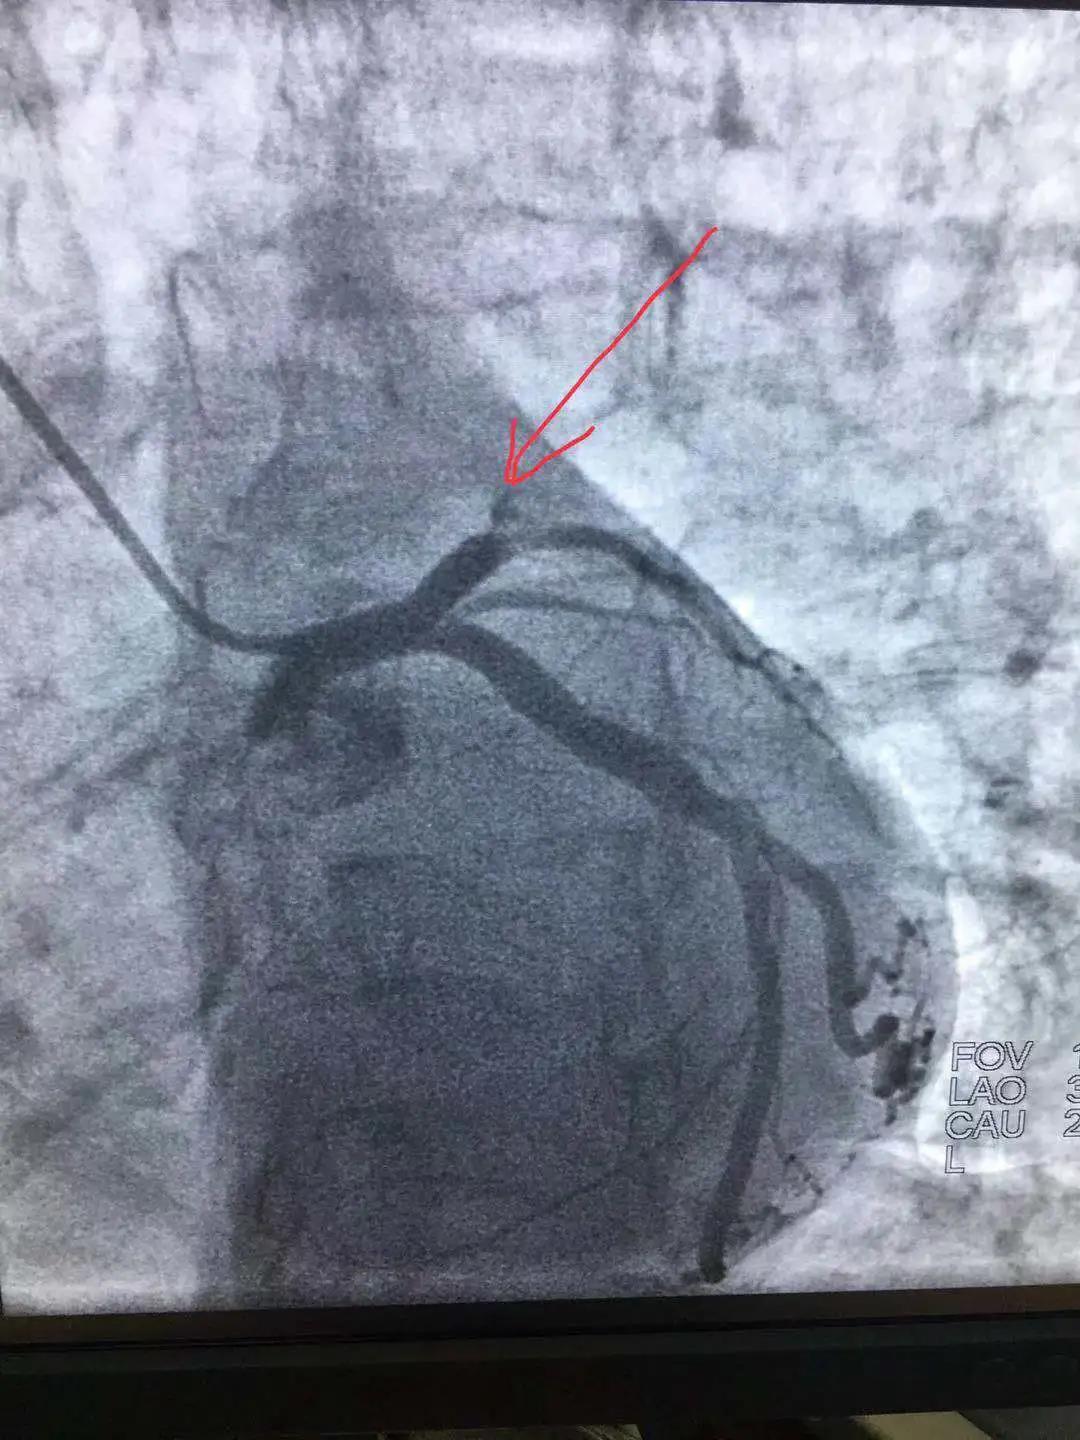

心內(nèi)科醫(yī)務(wù)人員冠狀動脈造影中

“冠狀動脈造影”即“冠脈造影”,是診斷冠心病的一種常用方法,作為一種有創(chuàng)診斷技術(shù),它被稱為診斷冠心病的“金標(biāo)準(zhǔn)”。心內(nèi)科融無創(chuàng)與有創(chuàng)協(xié)同治療為一體,硬件設(shè)施齊全,配有美國GE大C型臂數(shù)字減影X線造影機(jī),心臟臨時(shí)起搏器、床旁監(jiān)護(hù)儀、除顫儀、自動分析心電圖等,設(shè)有心臟重癥監(jiān)護(hù)室(CCU),擁有1個(gè)獨(dú)立導(dǎo)管室,設(shè)有心內(nèi)科??崎T診、心內(nèi)科病房(現(xiàn)有床位71張)、心血管無創(chuàng)檢查室、心電圖室等部門。科室現(xiàn)已熟練開展冠狀動脈造影技術(shù),為心血管疾病患者帶來了福音。